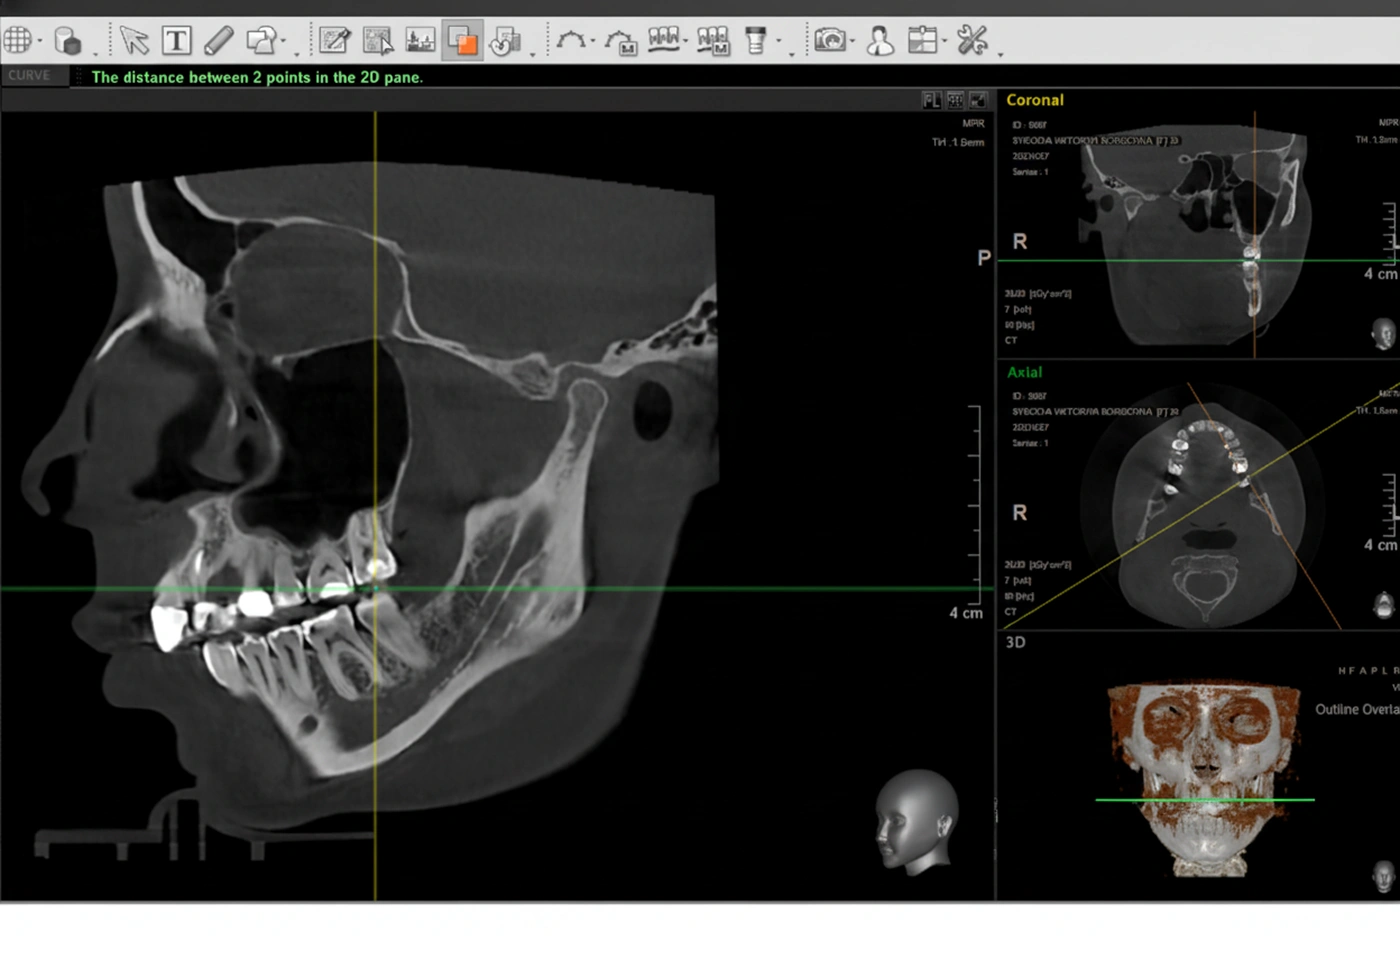

Перед началом лечения я провожу часовую первичную консультацию. Для этой встречи вам необходимо сделать «МРТ ВНЧС» и «КЛКТ двух челюстей с захватом ВНЧС в привычном прикусе».

Во время консультации мы смотрим и анализируем ваши исследования. Я подробно объясняю строение ВНЧС, показываю все причинные факторы вашей проблемы, отвечаю на все вопросы «Почему?»

Далее я составляю комплексный план лечения, где подробно объясняю алгоритм дальнейших действий.

Цель этой консультации – вы должны понять этот диагноз также ясно, как понимает его любой доктор.